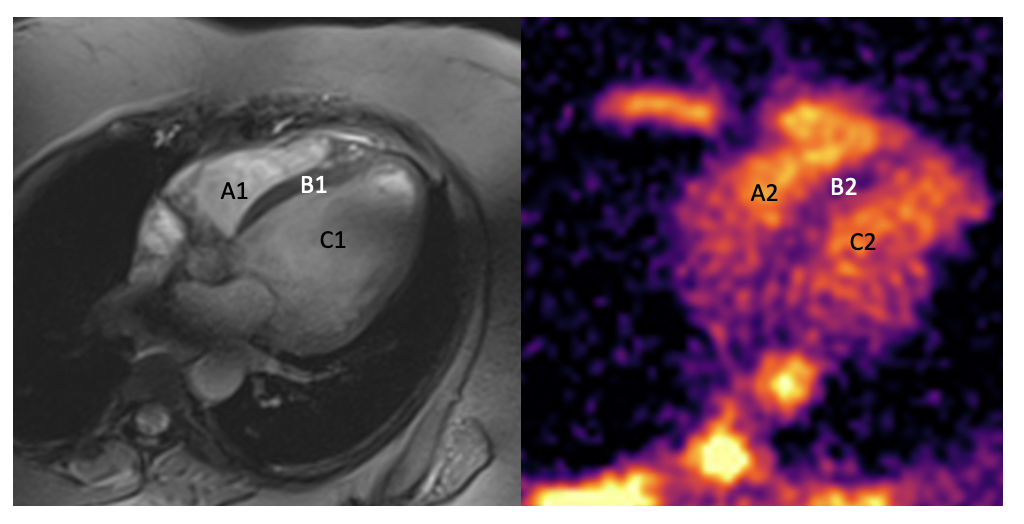

(A) Late gadolinium enhancement sequence at 1.5T showing transmural fibrosis in the lateral wall. (B) Sodium distribution map acquired at 7T, demonstrating focal 23Na accumulation in the corresponding region. (C) Signal intensity curve from the fibrotic area, illustrating increased gadolinium uptake. (D) Reproduced pattern of sodium accumulation in the same region, with concordant hyperintense signal. (E) Signal curve from normal septal myocardium, representing reference tissue pattern. (F) Sodium distribution in the septal region, showing a consistent normal pattern, similar to that observed in conventional tissue characterization..png)